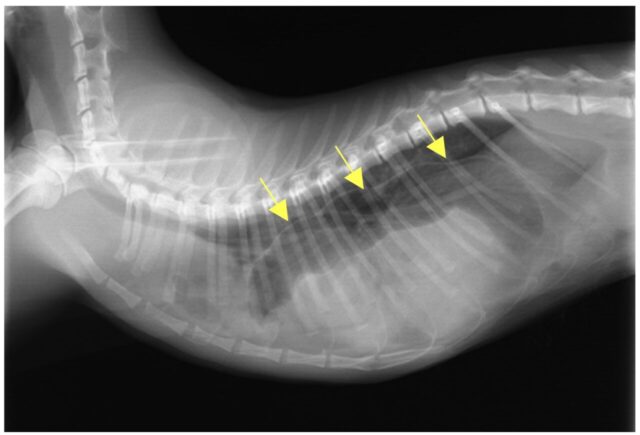

本症例の胸部レントゲン写真です。

突然の元気・食欲低下を主訴に来院され、身体検査では、呼吸促迫(呼吸が速い)、発熱が認められました。肺炎など呼吸器疾患や、消化器疾患、横隔膜ヘルニアなどを疑い、各種検査を実施したところ、レントゲン検査で、横隔膜のラインが消失し、お腹の臓器が胸へ入り込んでいる様子が認められたため、「横隔膜ヘルニア」と診断しました。